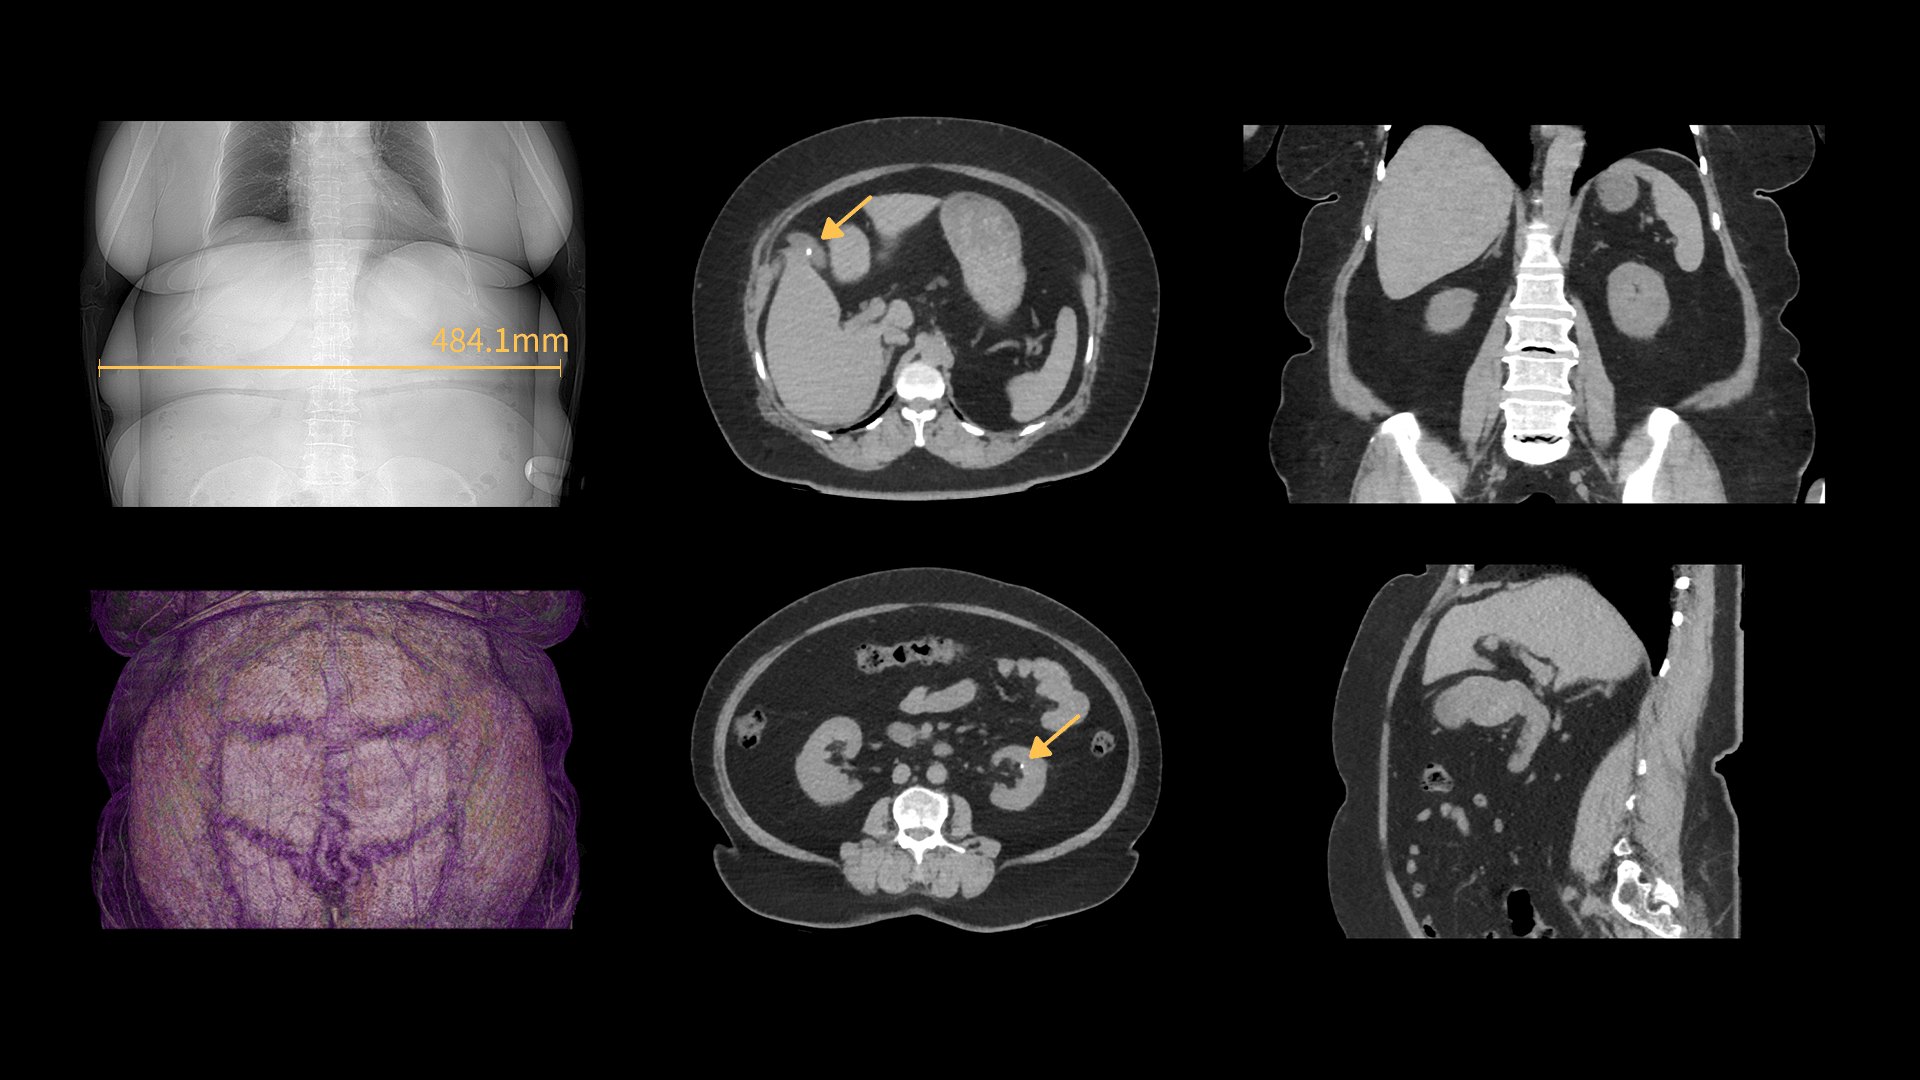

Imagistică Abdominală pentru Pacienți Obezi

Pacienții obezi au un volum corporal mai mare și un strat adipos mai gros, ceea ce reduce penetrarea razelor X și calitatea imaginii. uCT Orion Extra, prin tubul puternic și generatorul de înaltă tensiune, oferă imagini clare și precise chiar și pentru pacienții cu BMI ridicat.

| Parametri scanare |

BMI: 38.14 Timp rotație: 0.71 s / rotație kV: 120 mAs: 185 CTDIvol: 18.2 mGy Doză efectivă: 8.9 mSv |

| Parametri reconstrucție |

Matrice: 512 × 512 Grosime secțiune: 1.0 × 0.5 mm HIR: B_VSOFT_B WW/WL: 308 / -41 |